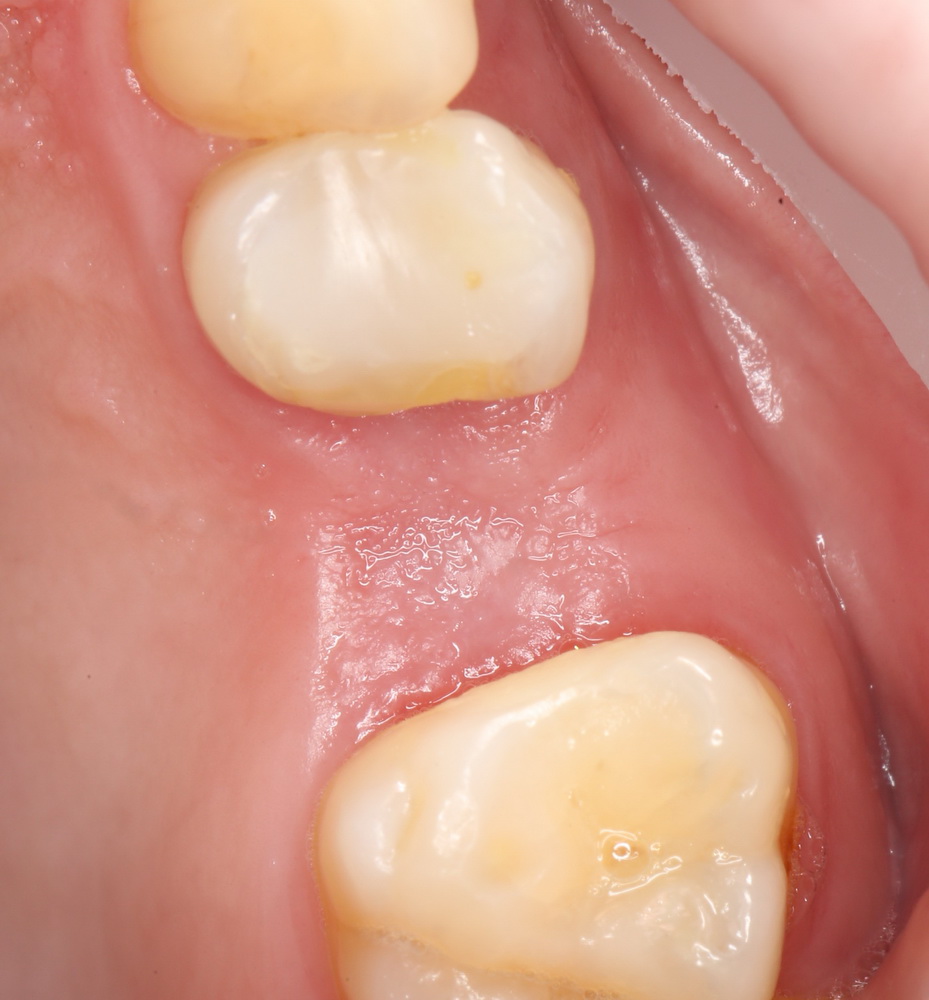

На приведенных фотографиях заметно, как изменились линейные размеры альвеолярного гребня с момента удаления 26 и установки импланта, до его интеграции (сравните толщину). Но это не так критично, и позволяет получить хороший результат протезирования:

Однако, если одной из задач имплантологического лечения является максимальное сохранение окружающих зуб тканей, то без использования биоматериалов вряд удастся обойтись. На фотографии ниже: вроде как, проведена немедленная имплантация, но последующая атрофия альвеолярного гребня вконец испортила эстетический результат лечения.

Не только фронтальная группа зубов требует внимания с точки зрения эстетики — некоторые пациенты хотят, чтобы и в боковом участке «зуб был неотличим от настоящего». И в этих случаях мы также используем биоматериалы, чтобы сохранить на месте костные стенки лунки и получить хороший эстетический и функциональный результат: